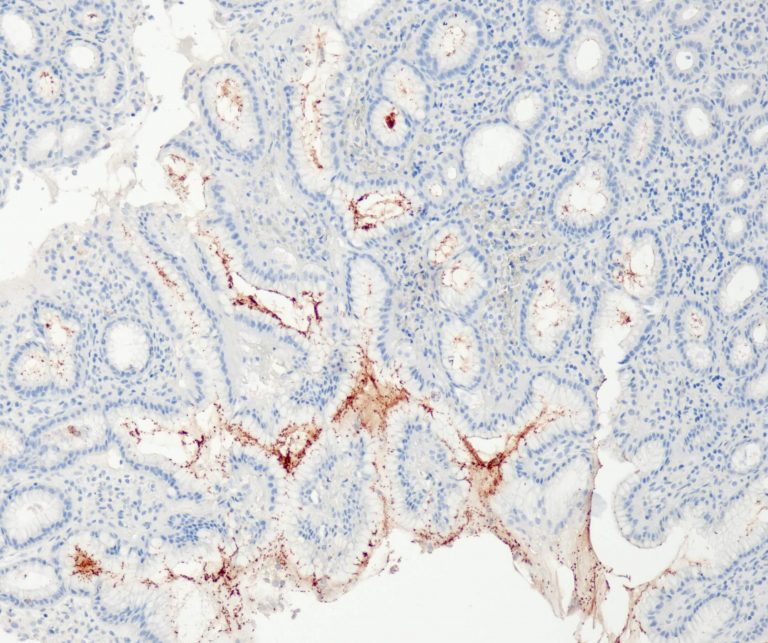

Vascular Pathology

Gastrointestinal (GI) Pathology

General Marker

Breast Pathology

Endocrine Pathology

Gynecological Pathology

Neuropathology

Infection Markers

Lung Pathology

Urinary Tract Pathology

Transplantation Pathology

Soft Tissue Pathology

Hematopathology